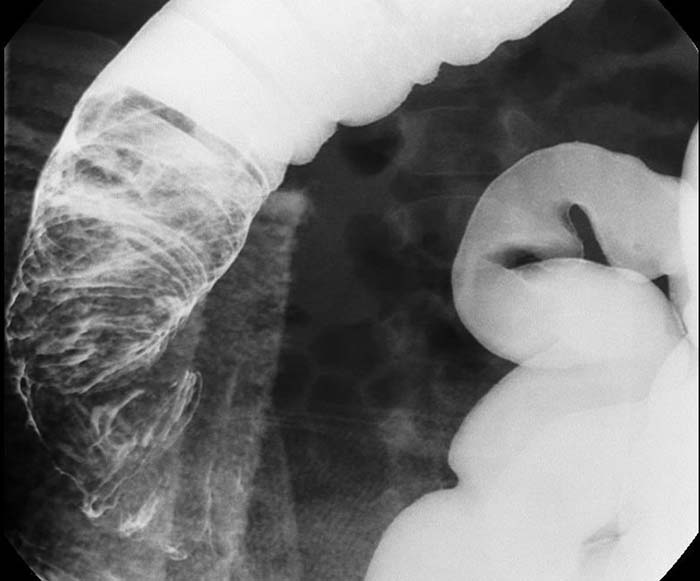

What is intussusception?

Telescoping of a proximal bowel segment into a distal segment, causing obstruction.

It compresses the mesentery, cutting off blood supply and causing necrosis.

Where does intussusception most commonly occur in children?

At the ileocecal valve.

Sudden severe abdominal pain, distension, vomiting, and a palpable right-sided mass.

What is 'red currant jelly' stool?

Stool mixed with blood and mucus, classic for pediatric intussusception.

Air or water-soluble contrast enema.